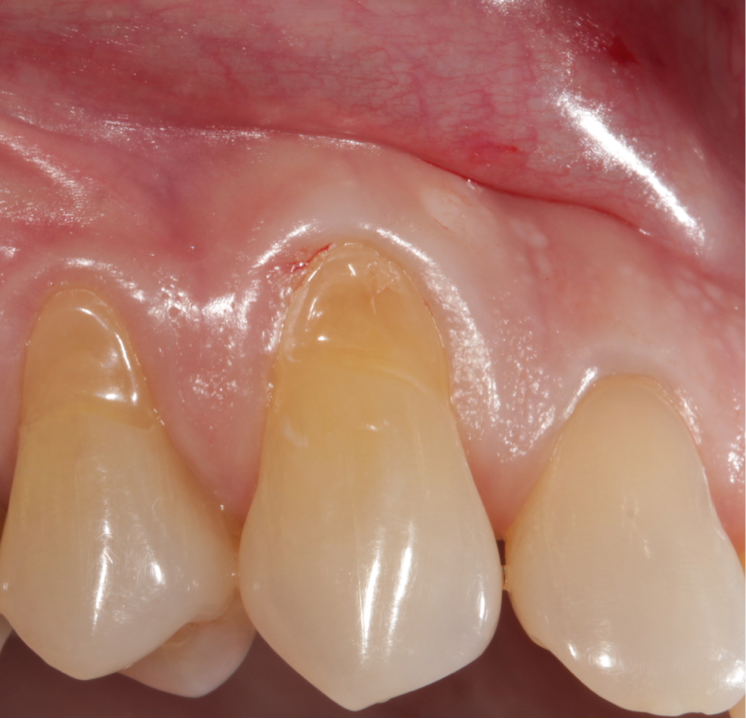

Diş röntgeni diş, çene kemikleri ve diş eti seviyesinin klinik muayenede görülmeyen kısımları hakkında fikir edinmek amacıyla X ışını yardımıyla elde edilen radyolojik görüntülerin adıdır. Diş röntgenleri tedaviye başlanmadan önce teşhis, tanı ve planlama amaçlı istenebileceği gibi, tedavi süresince ve tedavi sonrasında kontrol amaçlı olarak da istenebilmektedir.